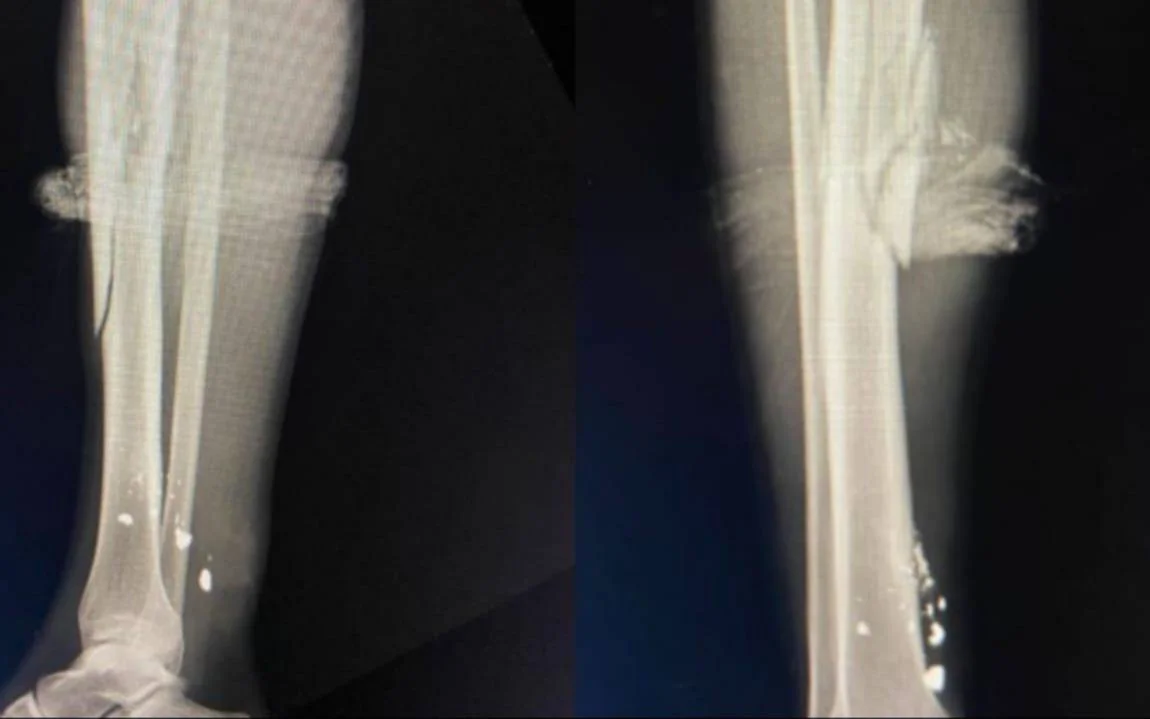

La situación se tornó aún más grave cuando uno de los asaltantes disparó dos veces, alcanzando al joven en la pierna. A pesar de la herida, ambos lograron llegar por sus propios medios al Hospital San Roque de Gonnet, donde recibieron atención médica. El diagnóstico reveló que el joven deberá enfrentar una recuperación debido a una fractura de tibia.